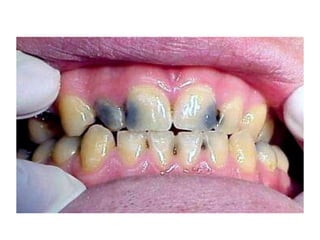

Dental caries, also known as tooth decay, is caused by certain types of acid-producing bacteria in the mouth that damage tooth structures when fermentable carbohydrates like sugar are present. It can lead to pain, tooth loss, infection, and in severe cases, death. While early signs may include white spots on teeth, untreated caries will form cavities. Risk factors include poor oral hygiene, frequent sugar consumption, dry mouth, and tobacco use. Treatment involves removing decay, restoring teeth, or extracting severely damaged teeth to prevent further destruction and infection. Preventive measures include proper brushing, flossing, limiting sugar intake, dental sealants, and fluoride therapy.